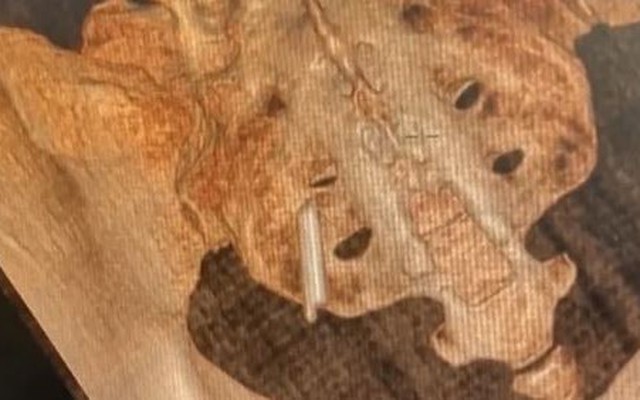

Tuy nhiên, vật thể này đã xuất hiện trong ảnh chụp CT 3D vào tháng trước sau khi cô Hu bị thương khi đạp xe và lo lắng về việc gãy xương cụt.

Khi các bác sĩ quan sát hình ảnh chi tiết, họ thấy rõ hình dạng của mảnh nhiệt kế bị vỡ nằm kẹt phía sau xương chậu của cô.

Bác sĩ Shang Ranran, bác sĩ điều trị tại Bệnh viện số 1 Vũ Hán, cho biết: "Nó dài khoảng 2cm. Thật may là bên trong không có thủy ngân. Nếu không nó có thể gây ra ngộ độc thủy ngân và nhiều tình trạng nguy hiểm khác."